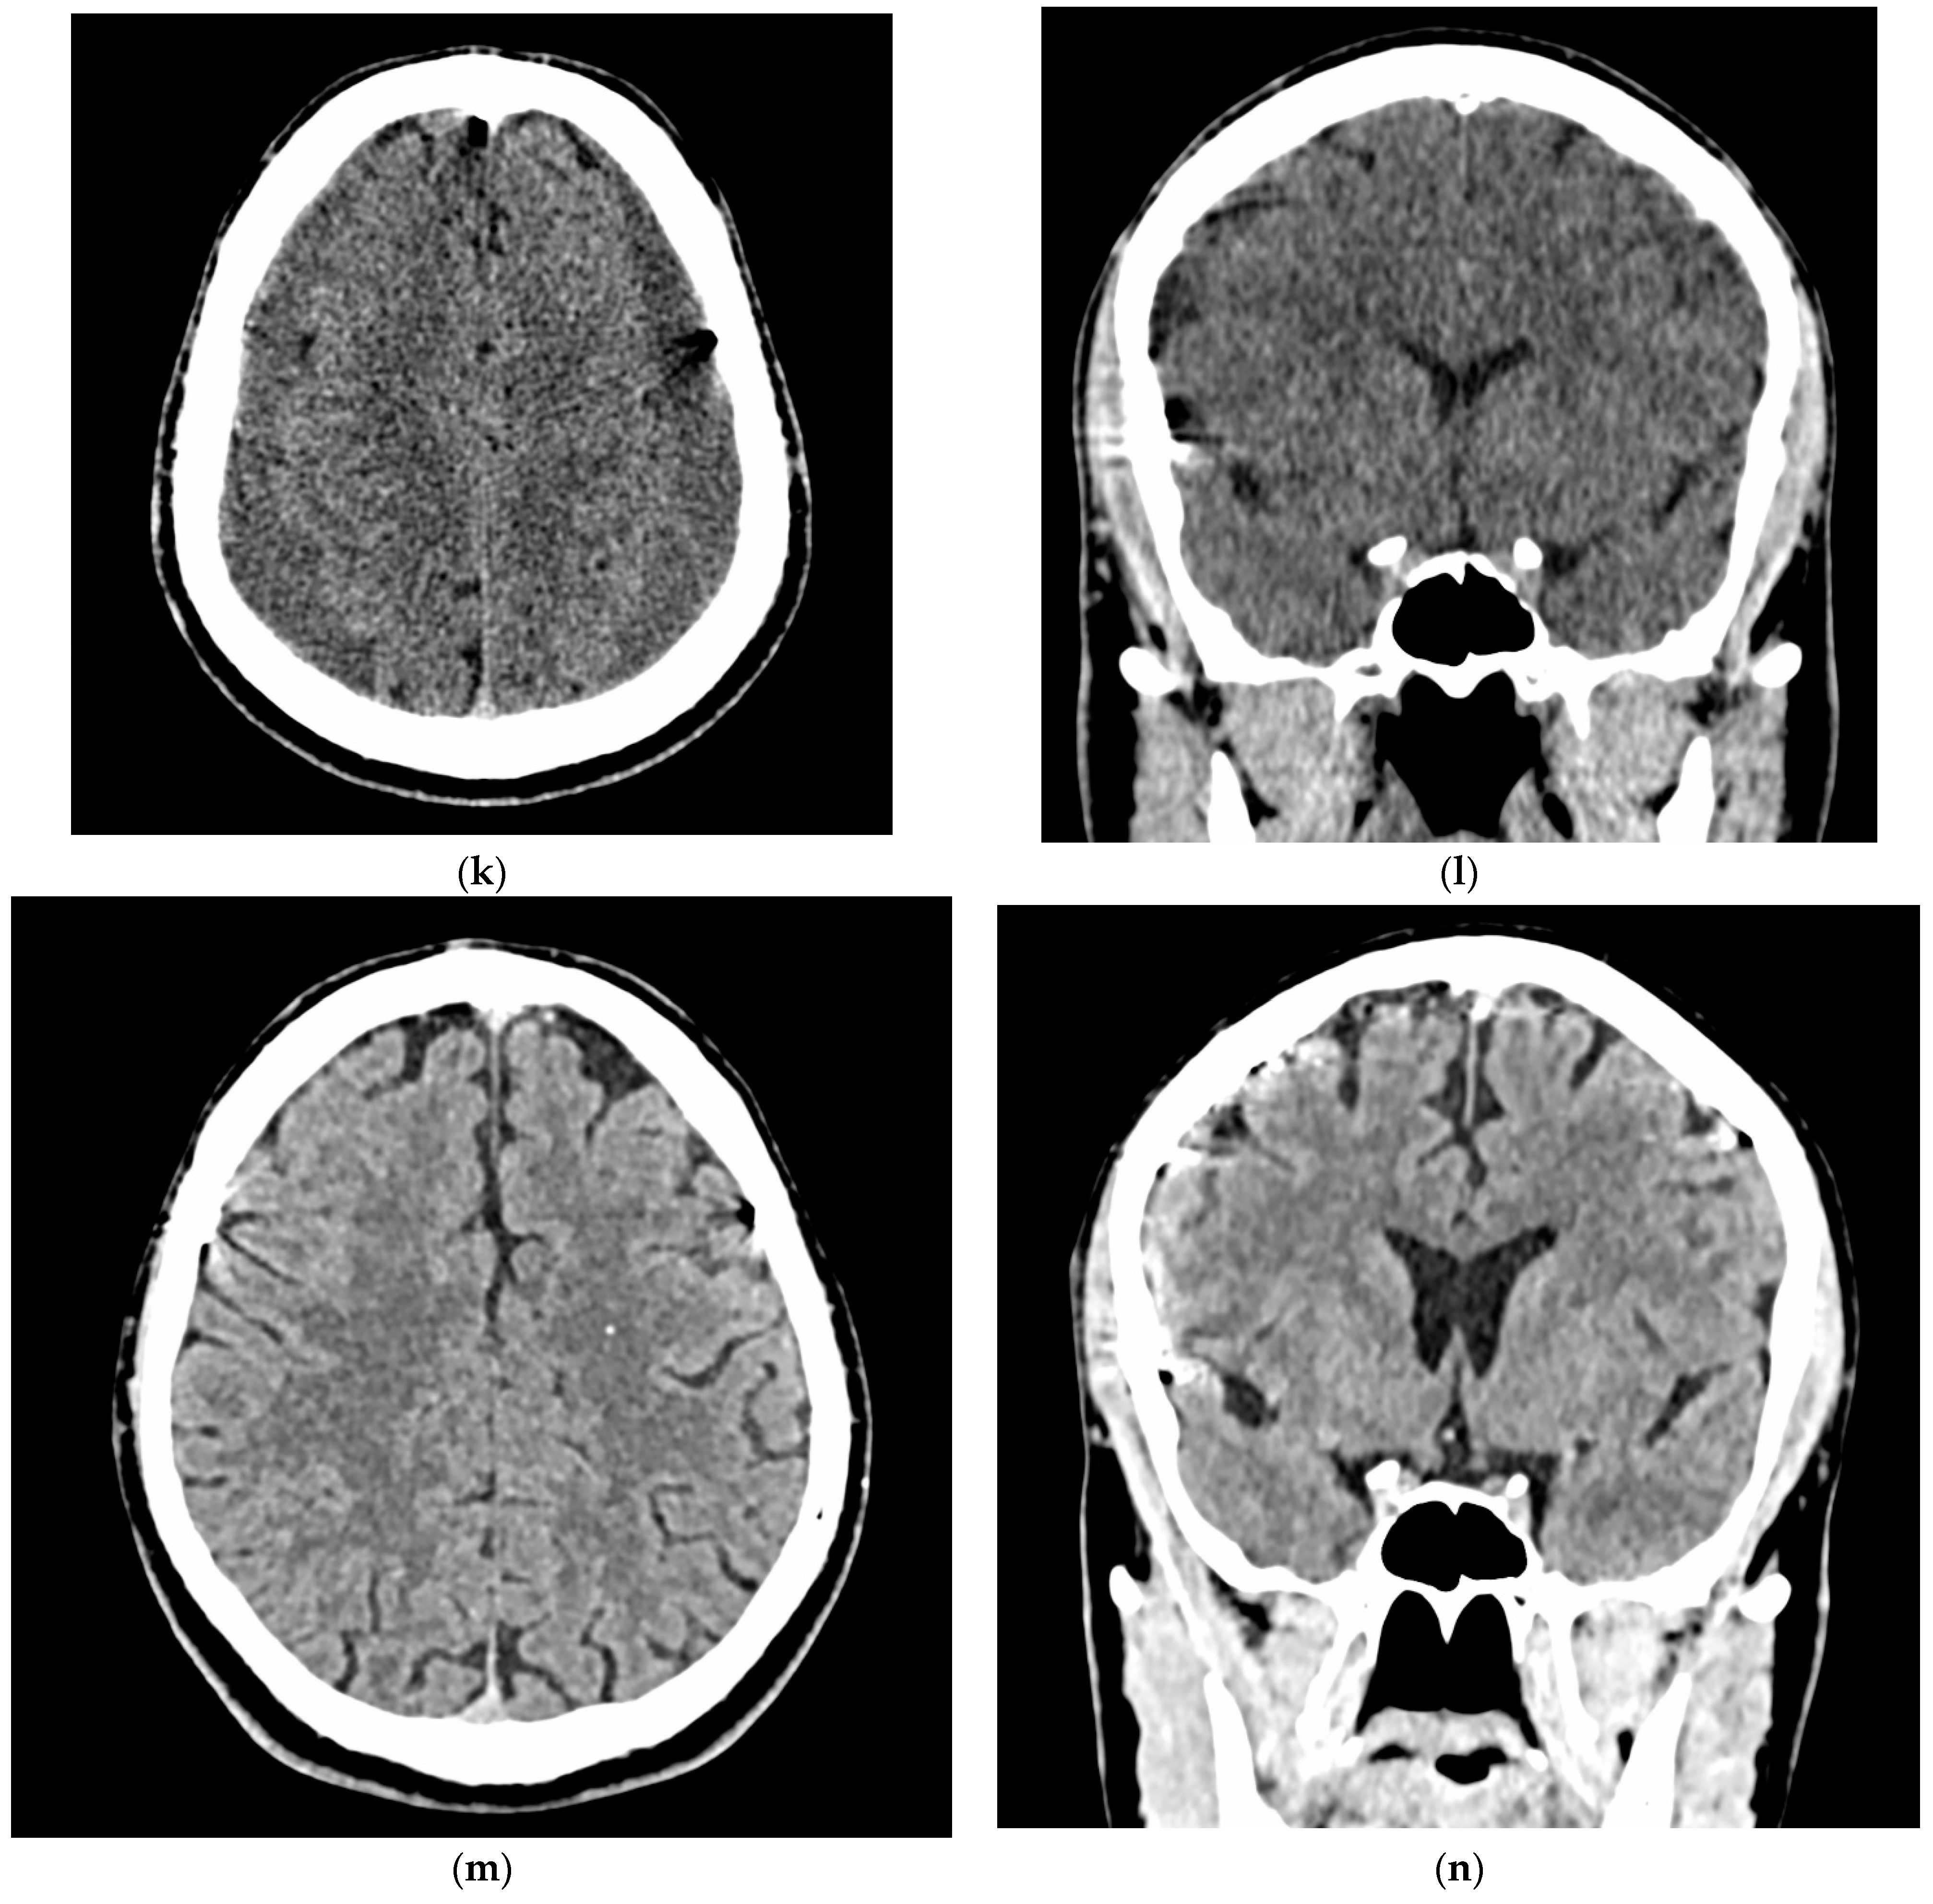

- A 70-year-old patient with left-handed CSDH and a midline shift of 12 mm, motor aphasia, and right-hand hemiparesis.

- A 42-year-old patient with bilateral CSDH that progressively increased during 1.5 months from 54 mL to 69 mL on the right-hand side and from 68 mL to 83 mL on the left-hand side, causing significant compression of both hemispheres and neurological deterioration.

- An 89-year-old patient with bilateral CSDH (no midline shift). There was no apparent connection with an antecedent head injury. However, the patient’s relatives reported that the patient did periodically fall. At the time of admission, the patient presented tetraparesis and a decreased level of consciousness.